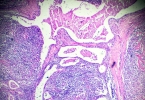

梅毒是一种危害性较大的性传播疾病,及时准确的检查对于诊断和治疗至关重要。以下为你介绍几种常见的梅毒检查方法。血清学检测梅毒螺旋体抗体检测:这是检测梅毒特异性抗体的方法,能检测出患者是否感染过梅毒。即使 ...